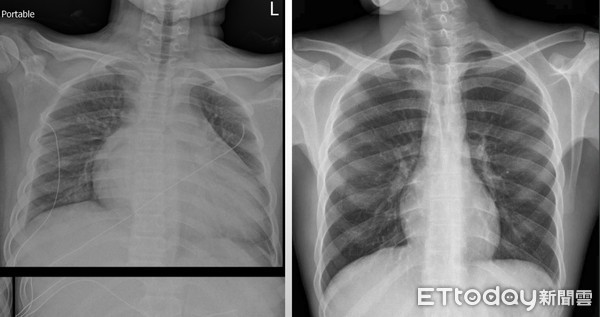

Ảnh chụp X-quang của Tiểu Lâm